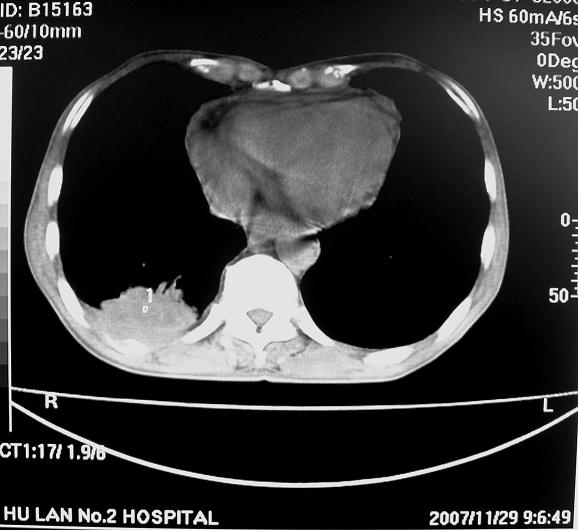

男63岁胸痛来诊

右下肺周围性肺ca并双肺及右侧胸膜转移。[emb6]

右肺病灶前缘不平整,略呈分叶状,其后方胸膜下脂线消失且似有向胸壁浸犯,左下肺球形灶内可见不规则空洞影,余双肺内可见多枚结节影,结合病史支持考虑肺癌肺内转移胸膜转移,便双肺后部病灶倒也是结核好发区域,建议穿刺活检

右下肺周围性肺ca并双肺及右侧胸膜转移。

右下肺癌伴双肺及胸膜转移。

左肺病灶内可见空泡征及典型的胸膜牵拉征,不排除原发周围型肺癌的可能.